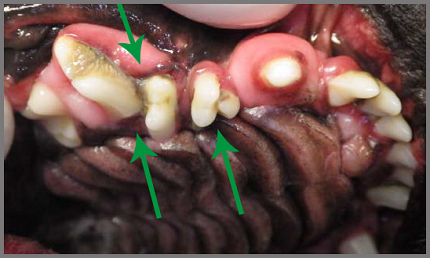

Bij een kortsnuitige hond staan kiezen dwars in de mond. Er is botverval en botontsteking onder het tandvlees, tandvleesontsteking en tandsteen (groene pijlen). Het tandvlees is verdikt en zit los.